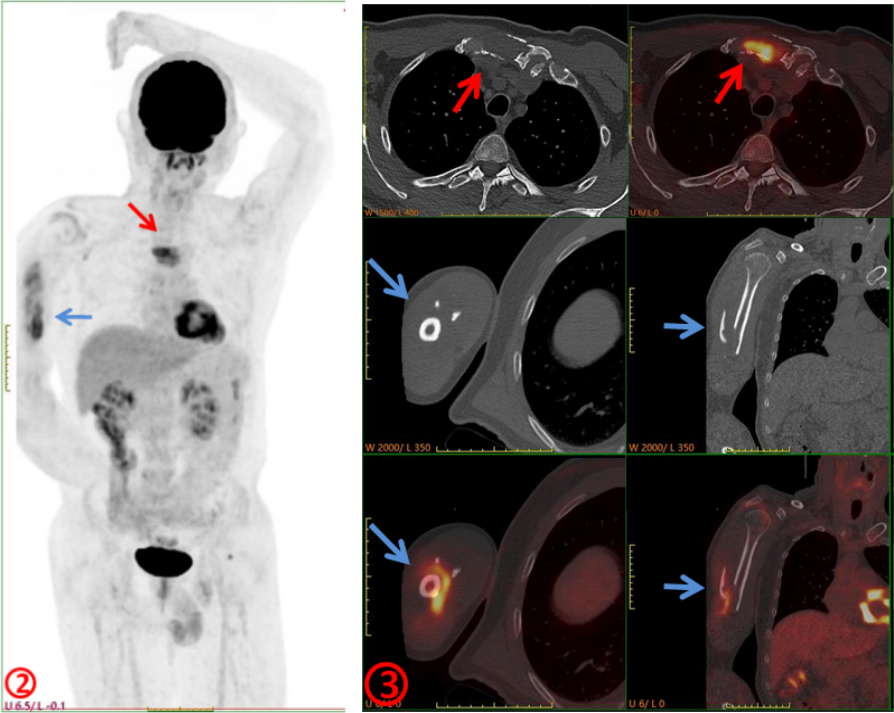

臨床初步診斷為惡性腫瘤骨轉(zhuǎn)移,遂行PET/CT進(jìn)一步檢查,示右側(cè)肱骨(圖2、3,藍(lán)箭)、胸骨(圖2、3,紅箭)骨質(zhì)破壞并代謝增高,SUVmax約6.0,余未見其它明顯異常病灶,考慮骨原發(fā)腫瘤(圖2)。隨后完善胸骨病變穿刺活檢及骨髓穿刺,病理示多發(fā)性骨髓瘤。

本例患者臨床初診考慮肱骨轉(zhuǎn)移,行PET/CT檢查目的是為了查找“原發(fā)灶”,以進(jìn)一步明確診斷及分期,指導(dǎo)后續(xù)治療。但PET/CT除肱骨病變外還發(fā)現(xiàn)了常規(guī)影像學(xué)沒發(fā)現(xiàn)的胸骨病變,同時(shí)未發(fā)現(xiàn)確切的原發(fā)臟器腫瘤,綜合考慮為骨原發(fā)惡性腫瘤,指導(dǎo)臨床進(jìn)行穿刺活檢,最終病理證實(shí)為多發(fā)性骨髓瘤。PET/CT是功能顯像,從代謝的角度提供信息,將可疑之處點(diǎn)亮,讓不起眼的病灶脫穎而出;同時(shí)是全身顯像,可以“一目了然”地了解全身各臟器組織的葡萄糖代謝情況,為診斷帶來新的思路,對(duì)腫瘤臨床分期、預(yù)后評(píng)估更準(zhǔn)確。